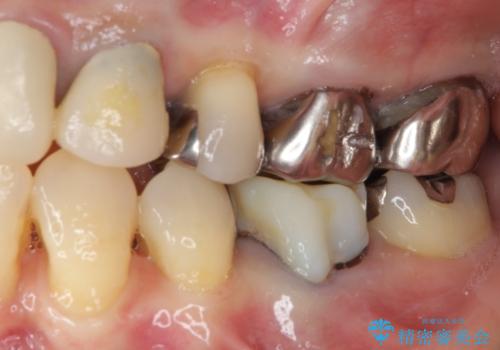

- 矯正治療を行った歯科医院で装着した前歯の仮歯が不快とのことで来院された患者様です。

仮歯自体はとても綺麗でしたが、2本の歯が欠損している部分に上唇小帯が入り込んでいたため、歯肉形成を行った上で仮歯を調整し、オールセラミックブリッジを装着することとしました。

他にも治療が必要な歯があったため、合わせてセラミッククラウンやセラミックインレーで治療することとしました。